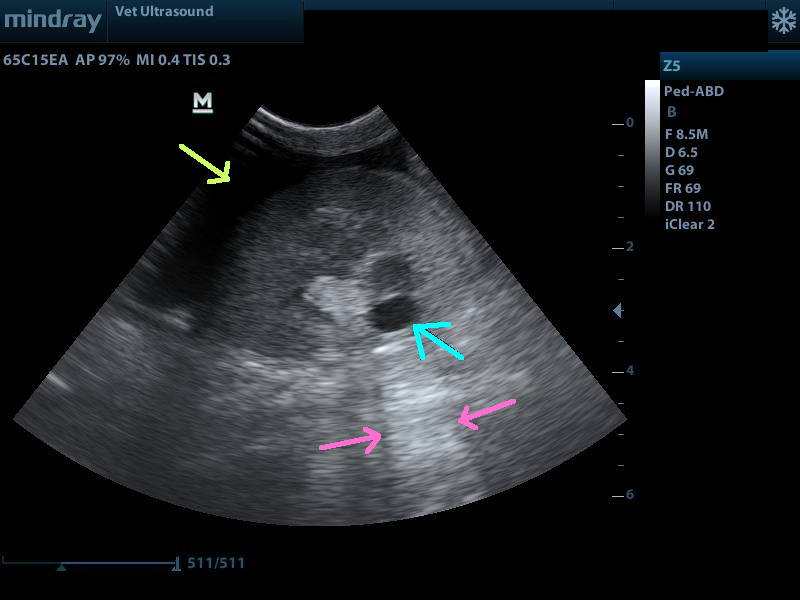

κίτρινο βέλος ελέυθερο υγρό στη περιτοναική κοιλότητα, μπλέ βέλος κύστη του νεφρικού παρεχγχύματος, ροζ βέλη ακουστική ενίσχυση ( επιβεβαίωση πως πρόκειται για κύστη και όχι για κάποια υποηχογενή μάζα).